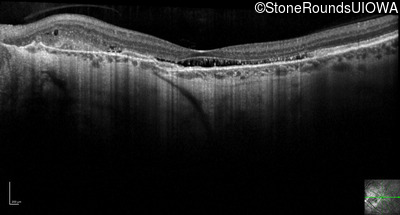

Optical Coherence Tomography - Right - 20/20 -3 sc

Exemplar / OCT Stack